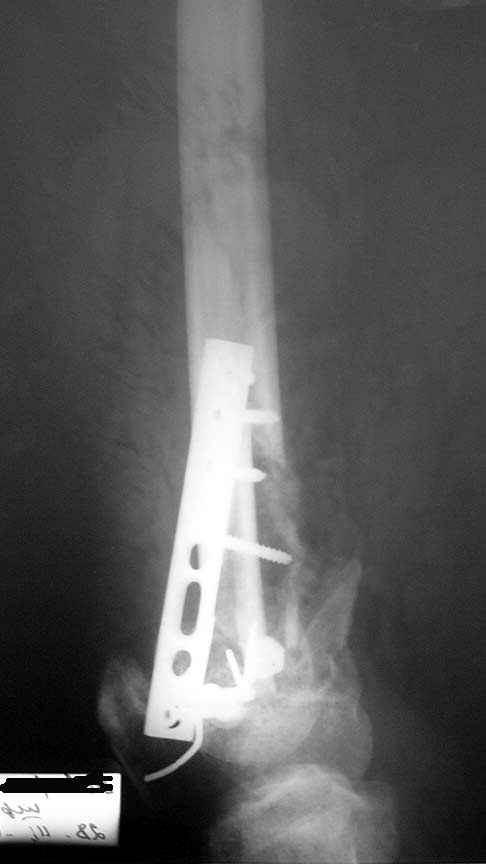

падение с высоты 7-го этажа, медсестра, молодая женщина 31 года.

падение с 7-го этажа 01 01 05. Молодая женщина 31 года,медсестра при падении с 7-го этажа получает только открытый многооскольчатый перелом метаэпифиза правого бедра. При поступлении удалены нежизнеспособные осколки,сформировался дефект кости. Выполнен остеосинтез из "того Что было" Раны зажили. Кокситная повязка. В которой наступило смещение отломков.Сейчас консолидация слабая,несостоятельность боковых связок коленного сустава, крестообразные связки держат. Кт для обследования нет. Что делать дальше-еще выжидать или пытаться активно помочь, и как?